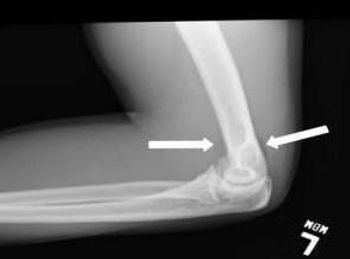

Alpine skiing, snowboarding, bobsledding, ice hockey … the ongoing Winter Olympics in Sochi serve as a cold reminder that injuries plague athletes around the world. Test your knowledge of common sports injuries here.

Bone problems run the gamut from low bone density and osteoporosis to sports and exercise injuries to congenital disorders. Take this week’s photo quiz to test your knowledge of bone disease and related concerns.